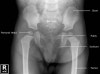

소아의 골반, 고관절, 대퇴골의 X-ray

- Pelvis AP view

- 3 Lines

- Acetabular angle

The acetabular angle using Hilgenreiner's line should be less than 28 degrees at birth.

The angle should become progressively shallower with age.

The normal range is 33 to 38 degrees.

Angles above 47 degrees are seen in patients with acetabular dysplasia.

A measurement between 39 and 46 degrees is indeterminate.